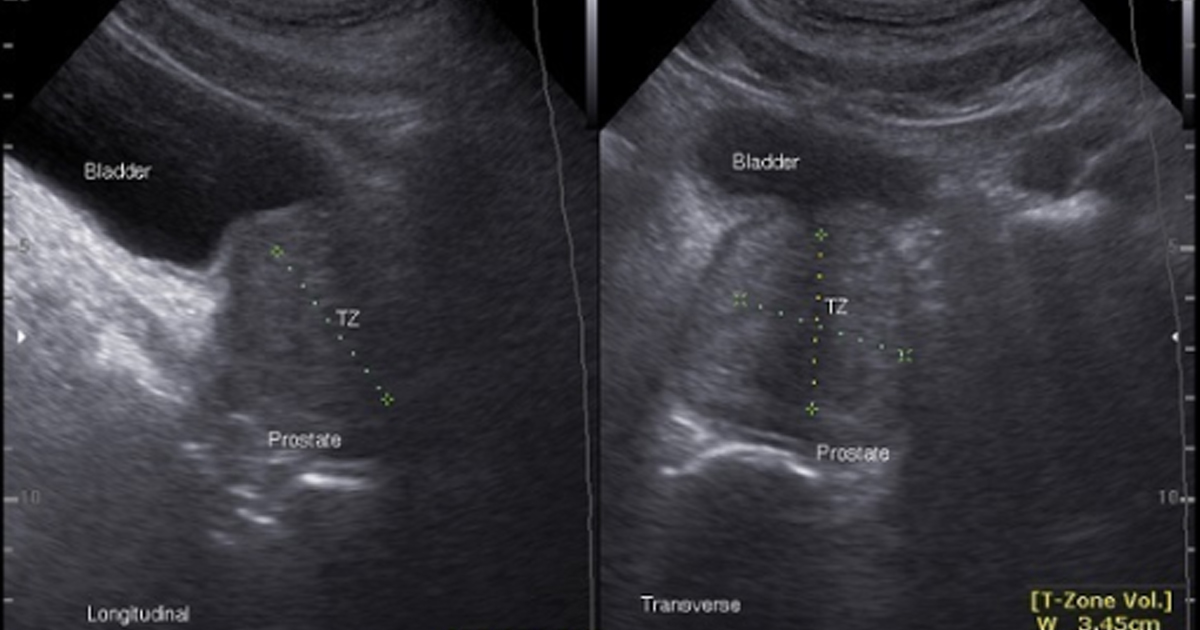

En el caso del ultrasonido, técnica ampliamente utilizada por su bajo costo y disponibilidad, la especificidad tradicional es limitada debido a la superposición entre lesiones malignas e hiperplasia benigna o prostatitis. Los modelos de aprendizaje automático o machine learning y aprendizaje profundo o deep learning han permitido mejorar la detección de lesiones sospechosas mediante redes convolucionales que identifican regiones de interés en tiempo real y reducen la dependencia del operador. Algunos sistemas han alcanzado sensibilidades superiores a 90% y han mostrado capacidad para disminuir biopsias innecesarias, especialmente en pacientes con niveles de PSA en la llamada zona gris.

La radiómica basada en ultrasonido también ha demostrado utilidad para diferenciar tejido benigno y maligno mediante la extracción de características cuantitativas de textura e intensidad. En estudios con cientos de pacientes, modelos como bosques aleatorios o máquinas de soporte vectorial han superado el desempeño del ultrasonido convencional y del PSA sérico en términos de área bajo la curva, lo que sugiere un potencial importante como herramienta complementaria en la toma de decisiones clínicas.